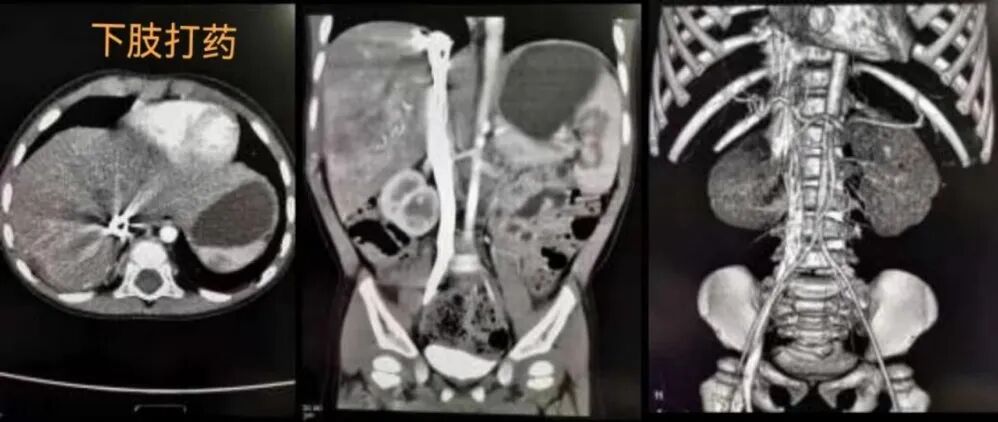

以下,我们就以图为例了解一下团注造影剂分别从右侧上肢及左侧上肢进入到人体内进行体循环的不同表现,以及从上肢和下肢进入体循环的不同表现来了解一下原因。

我们再看留置针打在上肢和下肢的情况:造影剂由下肢静脉注入,经髂静脉汇入下腔静脉,再进入右心房、右心室,最后回流到肺动脉,完成肺动脉循环后再经肺静脉进入左心房,左心室,最后进入各级分支动脉,完成体循环。

这图像是留置针打在下肢的腹部CT强化患者图片。显示此时动脉期造影剂进入各级动脉后,不仅腹主动脉、肠系膜上动脉、肾动脉、结肠动脉等见造影剂充填,下腔静脉内同时也可见非常明显的造影剂显影,且由于流速快阻力大,造影剂呈放射状伪影,右侧膈肌下病变受伪影影响干扰诊断。